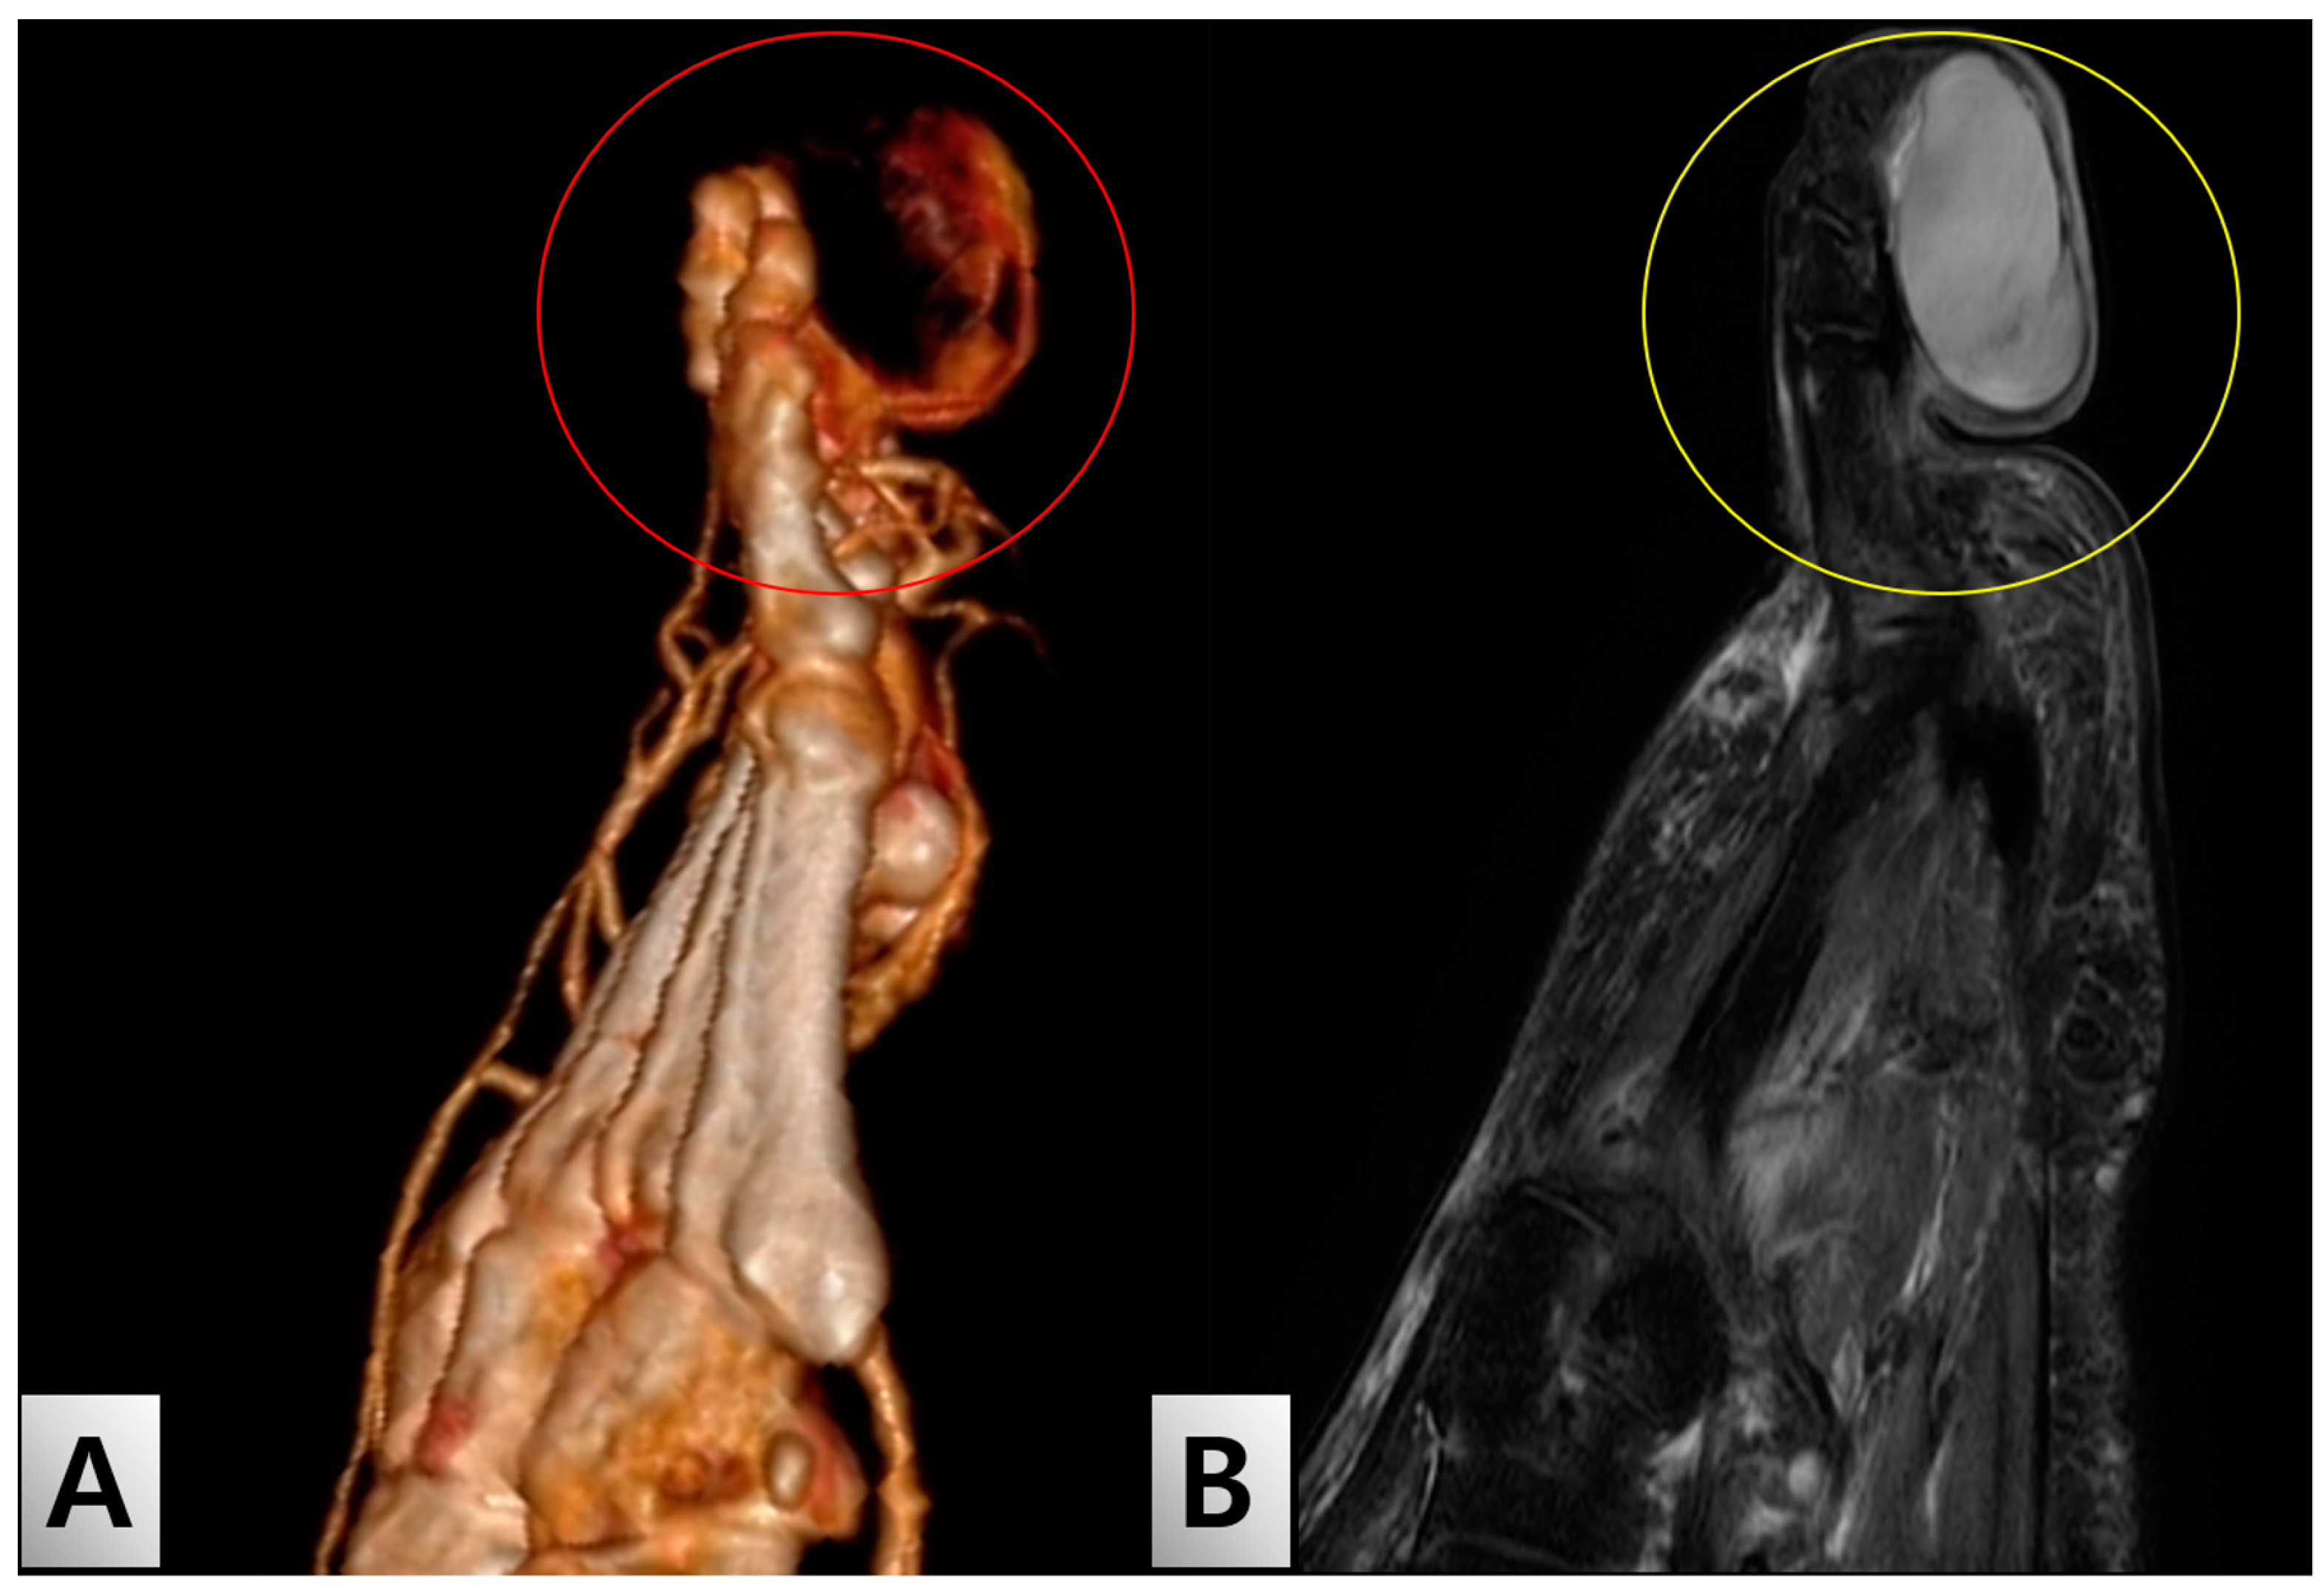

A Rare Case of Solitary Neurofibroma Misdiagnosed as Diabetic Foot Ulcer in the Toe Tip Region

2. Case Presentation